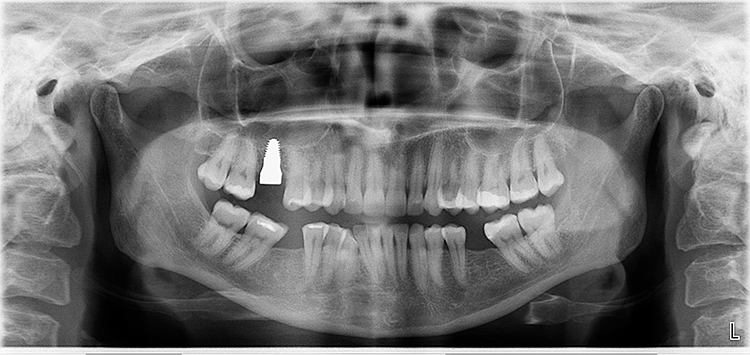

Abb. 2: Repräsentativer Fall von ABH Grad B Septus Typ II. a) Ansichten vor der Installation. Röntgenaufnahme der periapikalen Läsion an einem wurzelkanalbehandelten Molaren und klinische Ansicht der Typ-II-Socket nach der Extraktion. b) Die Ansichten nach der Installation zeigen das Implantat innerhalb des interradikulären Septums und das über dem Implantat platzierte A-PRF. c) Nachuntersuchungen nach 10 Tagen bzw. 2,1 Monaten. Die Röntgenaufnahme zeigt die Knochenbildung zwischen der Sinusmembran und dem apikalen Teil des Implantats. d) Jüngste Nachuntersuchung nach Einsetzen der Prothese.

Querschnittsbilder aus dem DVT zeigen eine hohe Genauigkeit und Zuverlässigkeit bei linearen Knochenmessungen im Zusammenhang mit der Implantatbehandlung [2]. Marginale Knochenniveaus wurden am Schnittpunkt zwischen der Längsachse des Implantats und der mesiodistalen Linie gemessen, die durch den größten krestalen Knochen auf jeder Seite des Implantats markiert ist und als Referenzpunkt für die Messung des Knochenverlusts bei Nachuntersuchungen dient. Trotz der begrenzten Anzahl von Implantaten und der Beschränkungen der Studie wurde eine Überlebensrate von 100% erreicht.

Bei dem balkonförmigen Implantat blieben die Alveolarkämme und der Kronenansatz erhalten (Abb. 4c und d). Der Spalt zwischen dem Implantat und der bukkalen Lamelle wurde mit A-PRF und einem Kollagenblock aufgefüllt, so dass keine zusätzliche Knochenaugmentation erforderlich war. Zusätzlich wurden PRF-Matrizen um, über, unter und neben dem Implantat im Knochen-Implantat-Raum positioniert (Abb. 1 bis 4b). Außerdem kam eine optionale Einheilscheibe (6 x 8 mm) zum Einsatz, um das Kollagen und die PRF zu sichern (Abb. 3b). Die Implantate zeigten bei einem Drehmoment von 35 Ncm Stabilität, welche mit dem Periotest-Gerät von Medizintechnik Gulden getestet wurde. Die Werte des Implantatstabilitätstests, die im Bereich von –8 bis 0 lagen, wurden als ideal für die Belastung angesehen (Tab. 3).

Der Erfolg der Implantate wurde nach den Kriterien des Pisa-Konsensus von 2008 bewertet [9]. Alle Implantate wurden als Gruppe I mit einem durchschnittlichen marginalen Knochenverlust von –0,1775 + 0,68 mm nach 1 Jahr Implantation eingestuft, die einen Knochenverlust von < 2 mm und keine Empfindlichkeit, Beweglichkeit oder Exsudat aufwiesen.